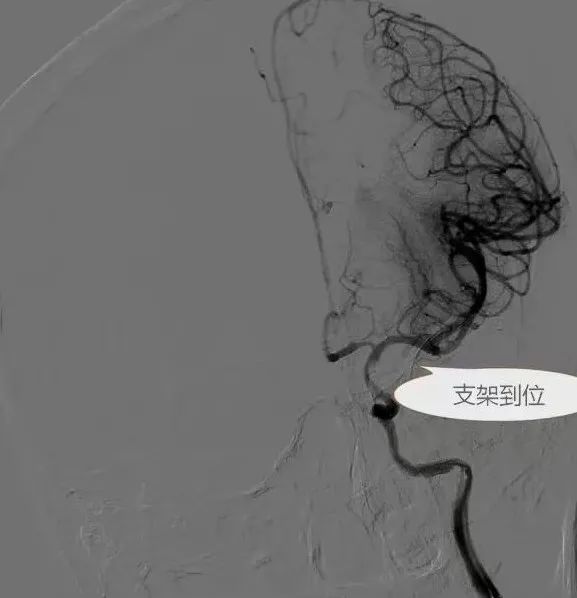

脑血管造影提示左侧颈内动脉海绵窦段闭塞,远端有侧枝代偿。

术中,赵德强主任凭借其精湛的技术和处理复杂血管病变的丰富经验,采用球囊扩张和支架置入技术,打通了闭塞的颈内动脉海绵窦段,血流恢复正常。